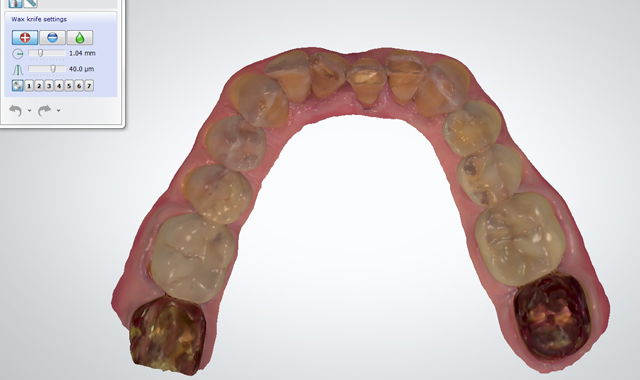

Fig. 3

Fig. 4

An initial scan of the patient’s preoperative condition was completed using a digital intraoral scanner (3Shape TRIOS) (Figs. 3-6). This eliminated the need for traditional analog impressions.2

Using dental CAD software (3Shape), the scans were manipulated to virtually alter the patient’s existing dentition into the final restorative state, create a digital diagnostic wax-up, and demonstrate treatment options to the patient (Fig. 7), all without patient discomfort or the time-consuming steps involved with traditional impressions and models.The proposed treatment involved placing milled monolithic lithium disilicate (IPS e.max CAD, Ivoclar Vivadent) full-coverage crown restorations on seven maxillary teeth (#6 through #12) and six mandibular teeth (#22 through #27). The patient approved the treatment plan.